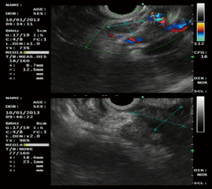

(1)病例特点:患者男性,69岁,以"消瘦厌食伴上腹胀3个月"于2013年1月9日收入我科,查体:未见明显阳性体征。既往史:无相关病史。实验室检查:肿瘤标志物AFP、CEA、CA19-9及其他生化检查未见明显异常。胃镜:十二指肠球部降交界移行处见隆起性病变,呈菜花样,表面充血、糜烂。超声胃镜提示:十二指肠隆起性病变(图7),活检病理回报:十二指肠黏膜慢性炎症。增强CT考虑恶性(图8)。(2)治疗:手术行胰十二指肠切除术。大体标本呈黄白色、鱼肉状、质硬肿物,边界模糊。(3)术后病理诊断为胰头炎症性肌纤维母细胞性肿瘤。(4)预后:术后电话随访4年余未见明显复发,恢复良好。